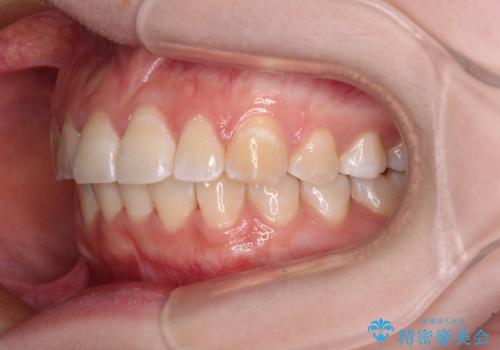

- 上下前歯のデコボコを気にして来院された患者様です。

ワイヤー矯正でもインビザライン矯正でも対応可能でしたが、インビザラインでの自己管理の煩わしさを避けるため、ワイヤー装置にて矯正治療を行うこととしました。

患者様も驚く、僅か10か月での治療終了となりました。

下顎前歯が1歯欠損しているため、上下正中は合わず、左右奥歯の咬み合わせは理想的とはならない仕上がりとなります。